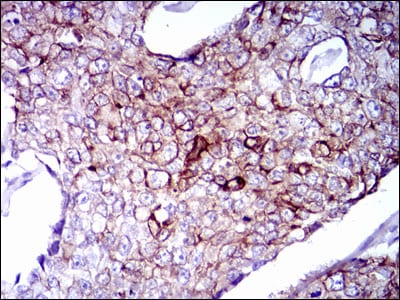

Immunohistochemical analysis of paraffin-embedded human breast cancer tissues using CK5 mouse mAb with DAB staining.